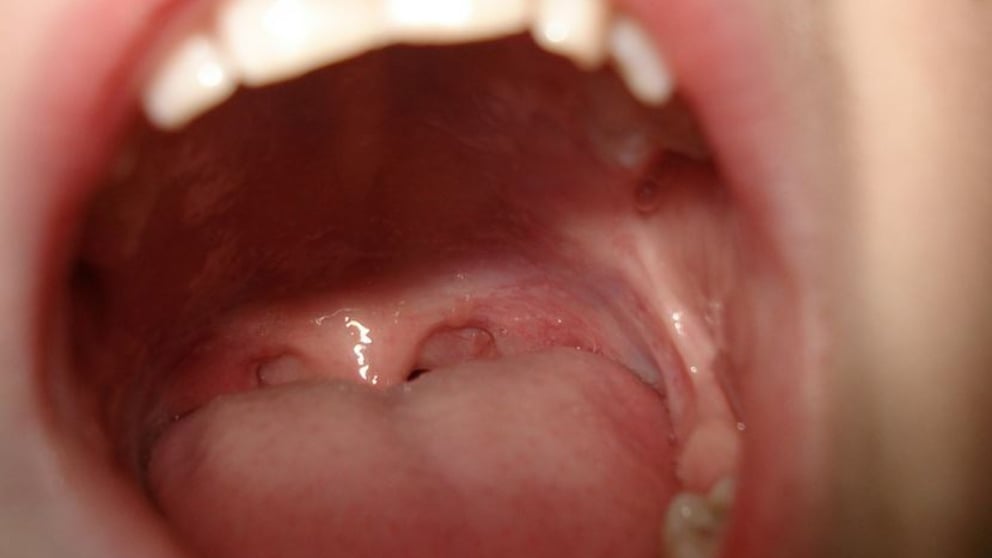

Se suele desarrollar en las superficies húmedas que recubren nuestra boca, nuestra garganta y nuestra nariz, a partir de células escamosas llamadas “carcinomas”. Eventualmente, también podría surgir de las glándulas salivales o piel de la cabeza.

Los síntomas del cáncer de cabeza y cuello suelen focalizarse en este último, al dificultarse tragar, experimentar dolor de garganta constante y agudo, notar cambios en la voz, advertir la presencia de llagas incurables, detectar bultos en el cuello y otras afecciones, casi siempre bien localizadas en esa zona.